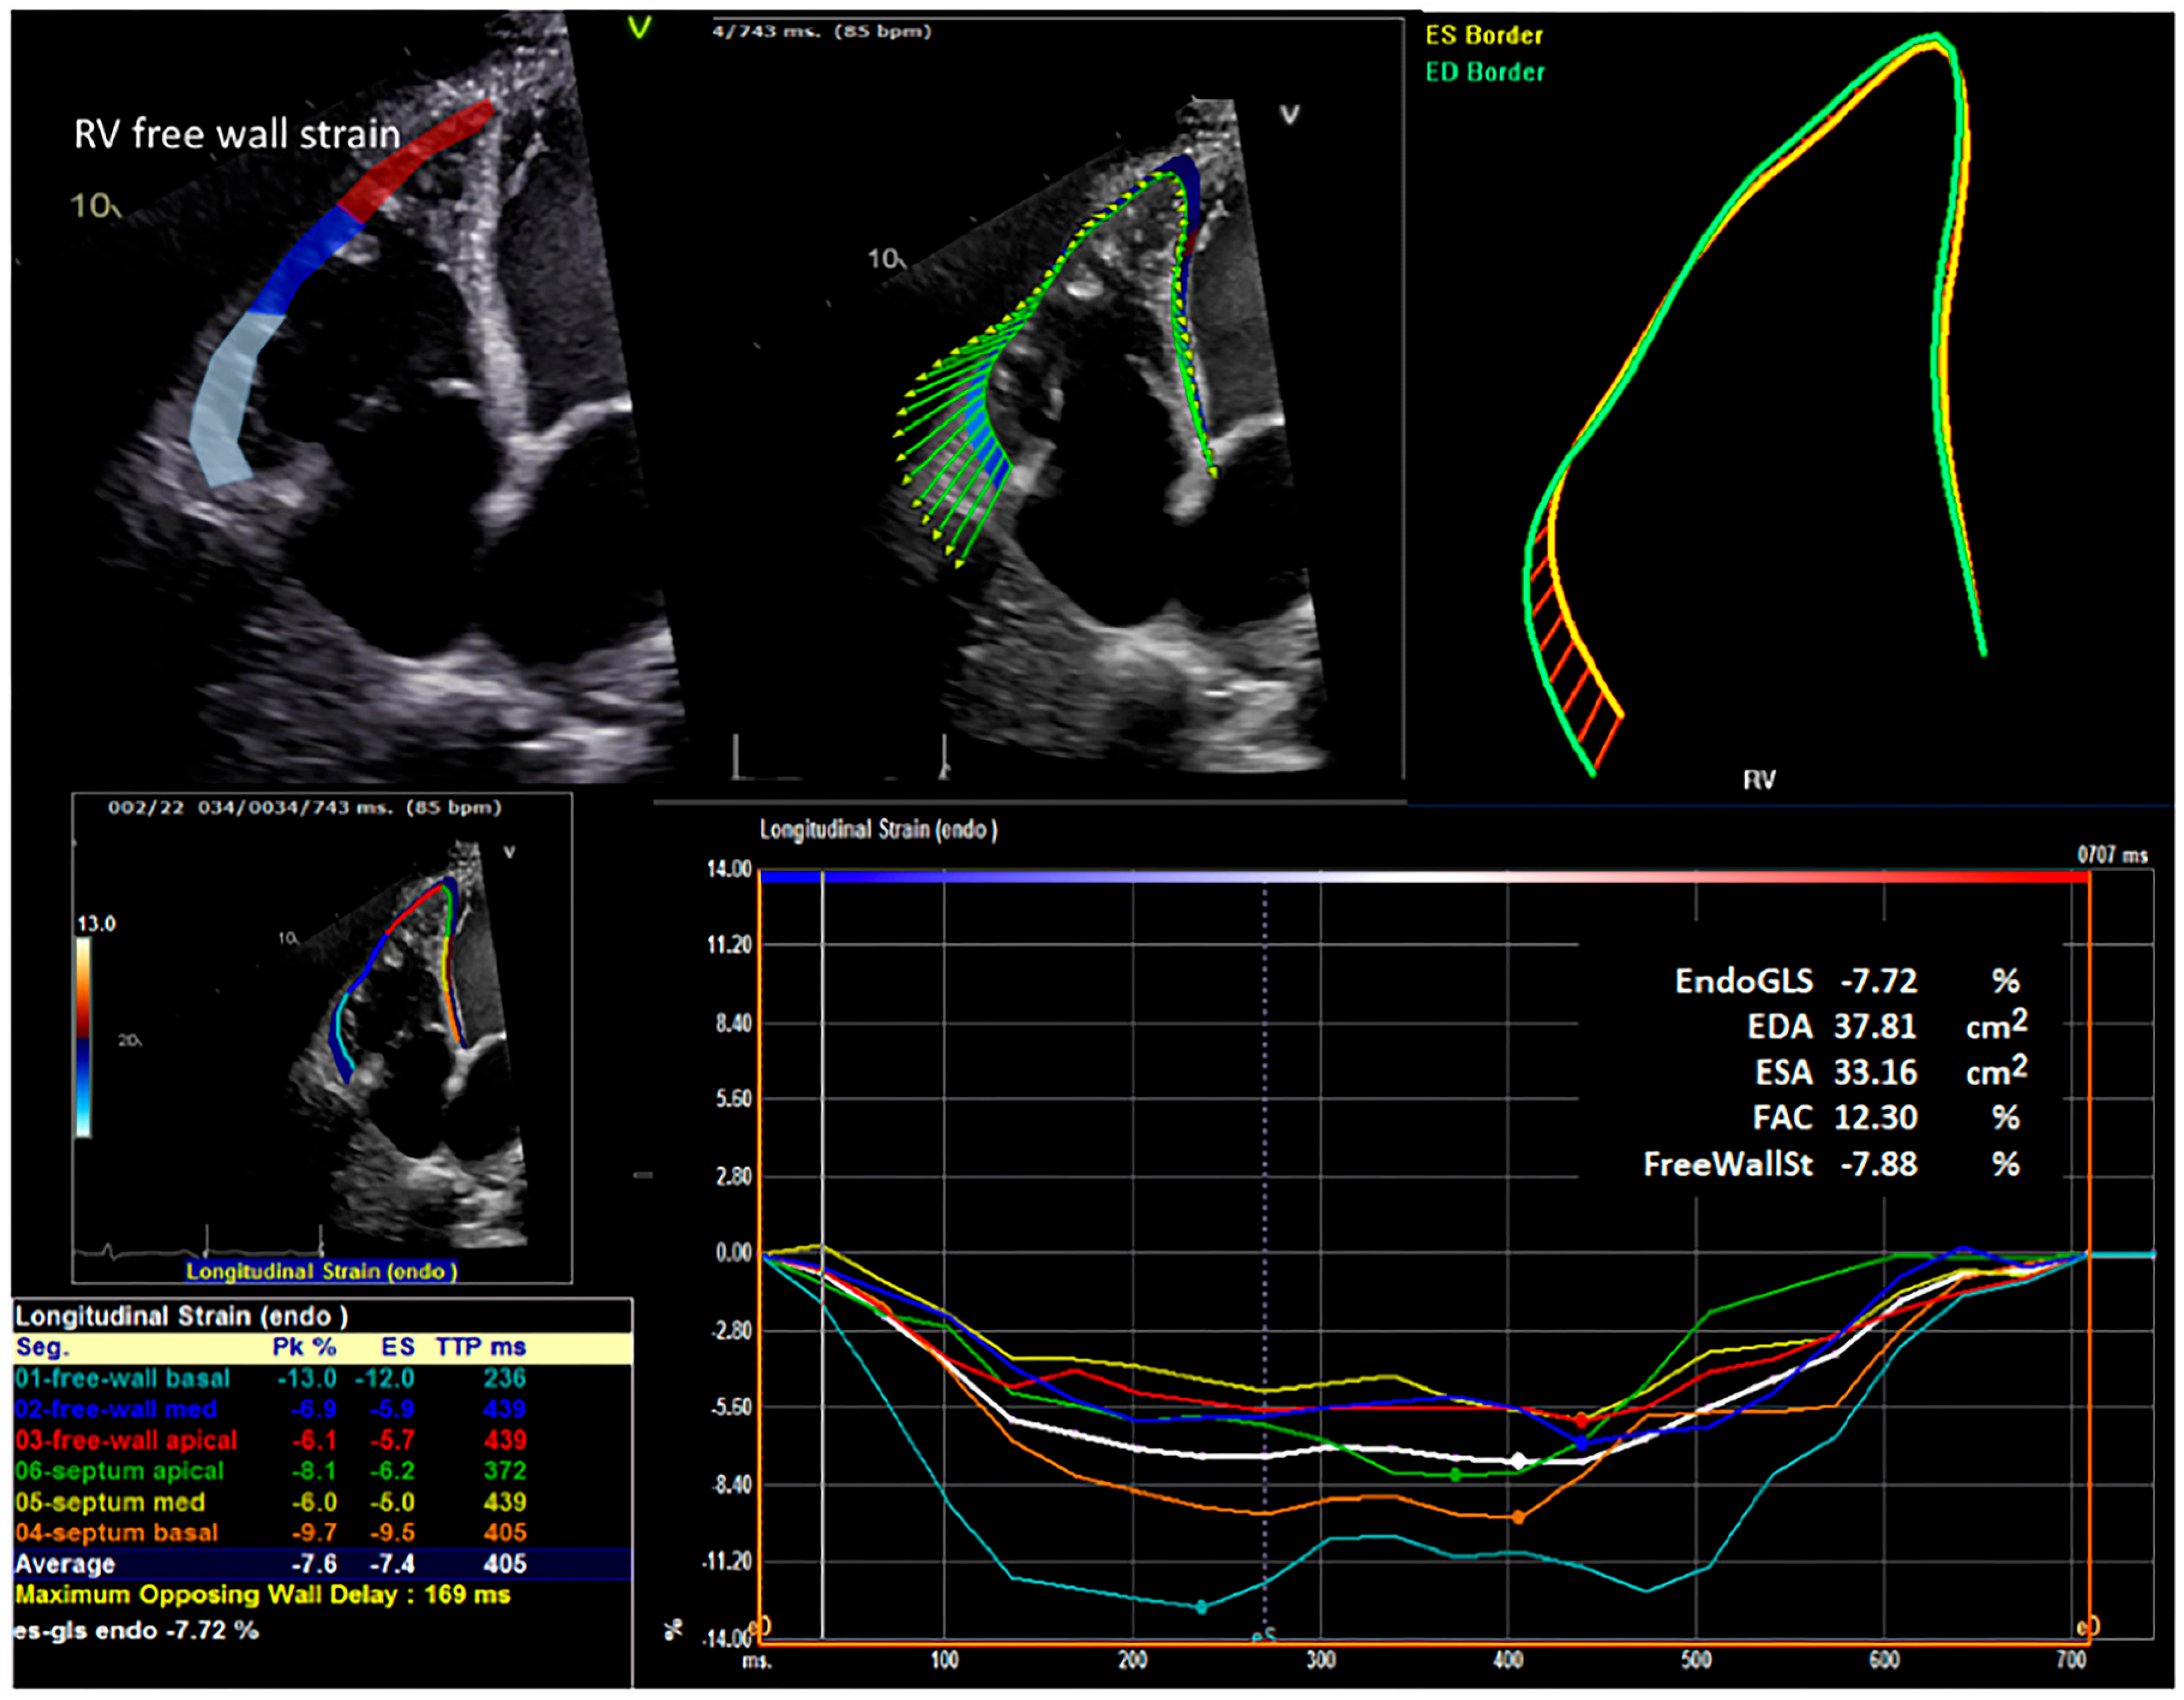

2.4. Strain Analysis

| Right ventricular free wall strain (%) | −5.1 | (−9.8, −3.9) | −6.7 | (−9.0, −4.5) | 0.40 |

| Right ventricular fractional area change (%) | 15.9 | (11.9, 21.9) | 19.6 | (12.6, 24.0) | 0.50 |

| Right ventricular free wall strain (%) | −8.0 | (−10.2, −5.1) | −6.0 | (−8.6, −4.2) | 0.07 |

| Right ventricular fractional area change (%) | 21.5 | (16.3, 27.7) | 17.5 | (12.7, 24.8) | 0.08 |